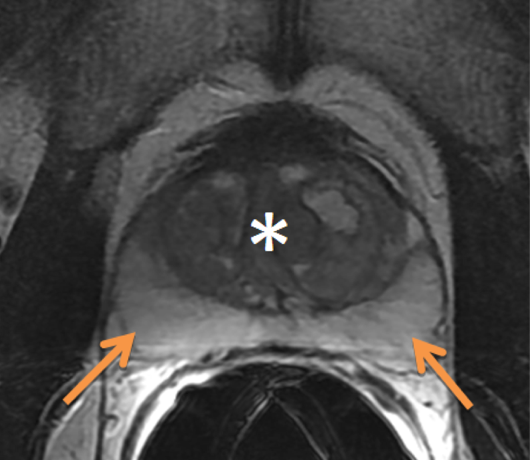

Imaging

Additional imaging studies include an MRI of the prostate, generally with endorectal coil. If the PSA is > 20 then a bone scan is reasonable. A transrectal ultrasound is an intrinsic part of the biopsy in recent years. Peripheral zone cancers can be seen on the ulltrasound with hyper-echoic lesions in 69% of the cases. CT of the pelvis and prostate are used in radiotherapy treatment planning. Discrepancies between CT and MRI on fused images may exist (Roach):

Poor correlation of the prostate apex was found between these modalities. The retrograde urethrogram was tested to insure that the urethrogram itself did not displace the prostate by pre- and post-urethrogram MRI studies which demonstrated no artifactual displacement as a result of the urethrogram. Roach examined 10 patients and noted that the prostate volume was 32% larger on non-contrast CT than when determined by MRI. The regions of most non-agreement were posterior-inferior (neurvascular bundles) and posterior extent of the gland. The CT volume for prostate and seminal vesicles was 40% larger on the average than the MR with the CT variant 8 mm larger at the base of the SV and 6 mm larger at the apex. This was corrected for and persistent with interobserver variation.